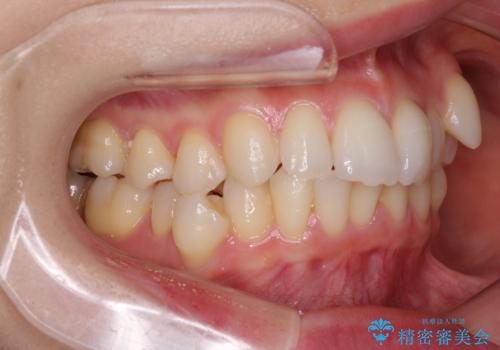

骨格的な左右差と、歯列から外れている歯が上下で左右非対称になっていることから、上下正中が歯1本分ずれている状態でした。

八重歯の改善と、上下の正中位置を極力合わせていくことを目的として、上下左右の第一小臼歯4本を抜歯し、ワイヤー装置にて矯正治療を行うこととしました。

アンカースクリューを用いて正中位置を調整したことで、上下の正中位置をほぼ一致させることができました。

移動量が多かったため、治療期間は長くなりましたが、大変満足のいく仕上がりとなりました。